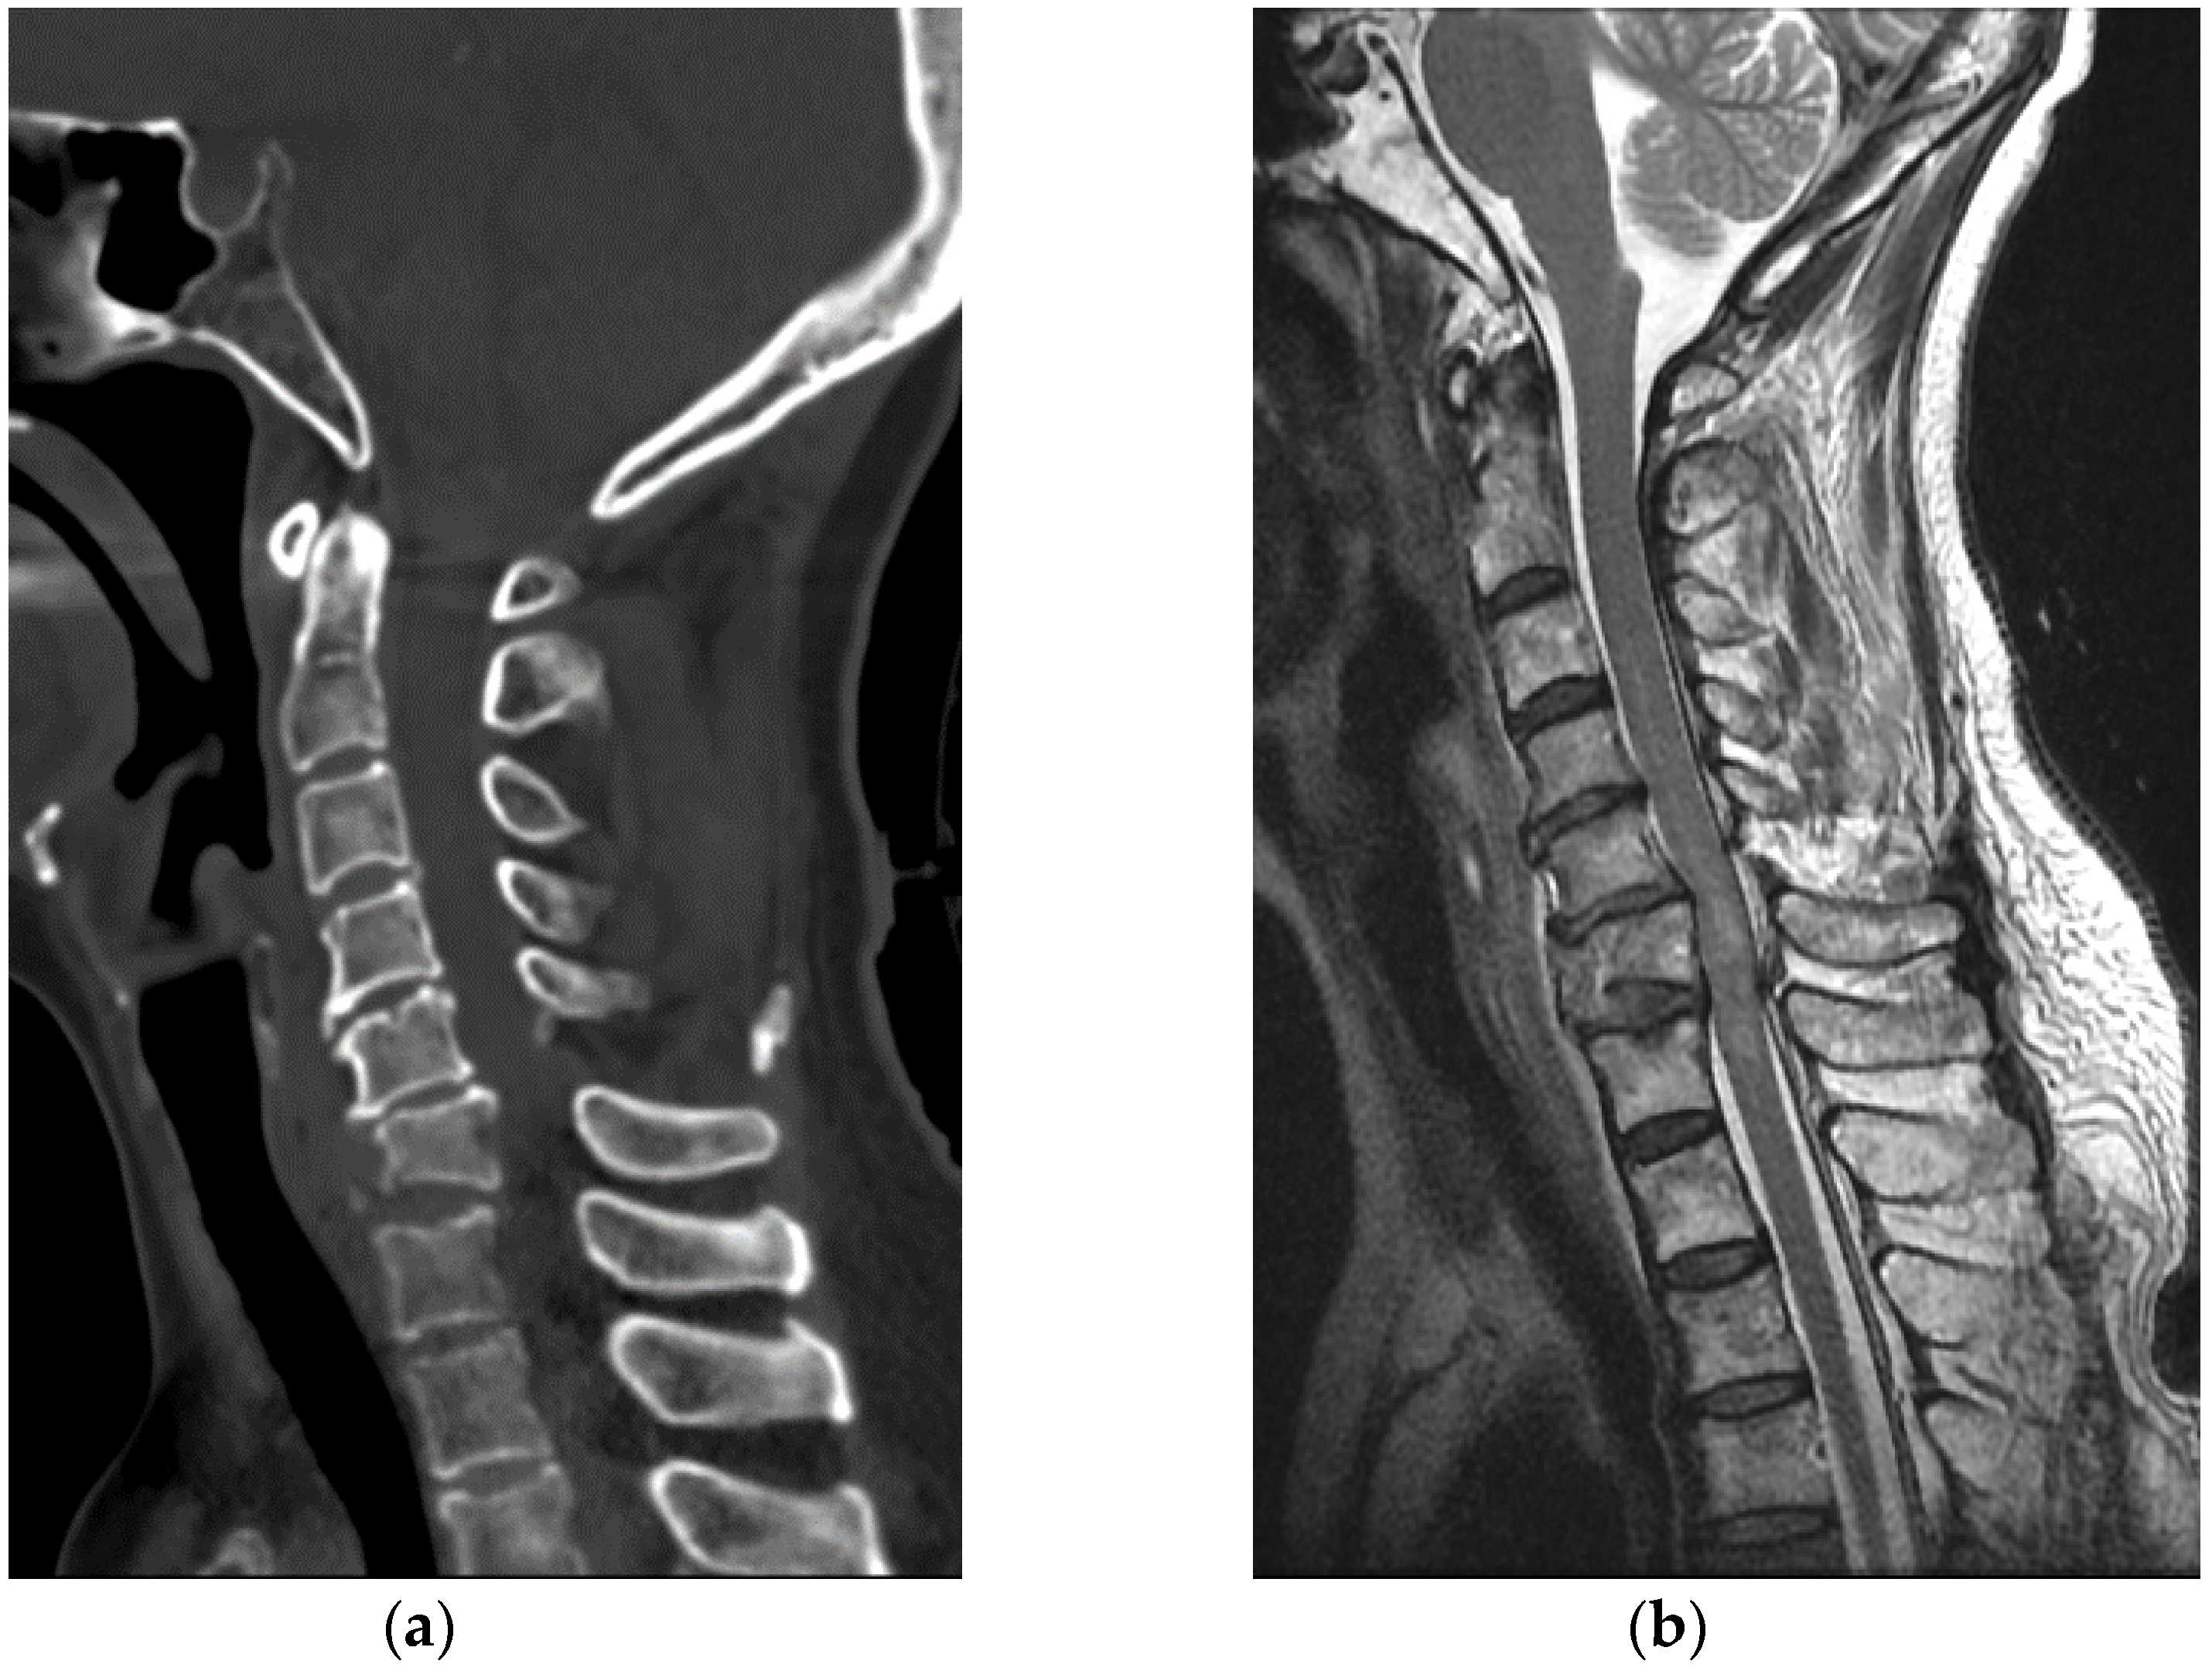

A 63-year-old healthy woman went to a nearby public health center with public outdoor exercise equipment on 23 March 2018. She had undergone right total mastectomy due to breast cancer in 2000 and had been active and capable of performing daily living activities before the accident. At the public health center, she tried the inversion table. Hanging on the inversion table upside down, her feet slipped out of her shoes, and she fell and hit her head on the ground. The patient collapsed and immediately experienced a total loss of motor power in whole body; she was found and transferred to the emergency room of a local medical center. Non-enhanced brain CT did not reveal any abnormalities. Cervical spine CT revealed dislocation of C5-C6 (Figure 5a). For emergent surgical management, the patient was transferred to our hospital. Cervical spine MRI revealed flexion distraction with translation injury at C5-6, leading to C5-6-7 cord contusion with an intramedullary hemorrhage and complete DLC disruption. (Figure 5b).

Figure 5. (a) Cervical spine CT showed C5-C6 dislocation with C6 vertebral body compression fracture; (b) Cervical spine MRI revealed flexion-distraction with translation injury at C5-C6, cord contusion with an intramedullary hemorrhage and complete DLC disruption.